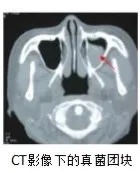

最终在小杨的头颅CT上发现了问题:

小杨的鼻窦腔内有好大一个团块,

几乎把整个鼻窦腔填满了,

鼻窦CT结果提示左侧上颌窦真菌感染。

所以小杨鼻窦腔里的团块

其实是一整团霉菌?!